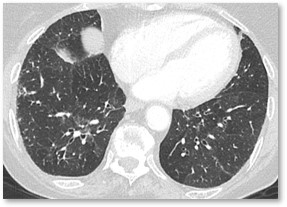

HRCT Gallery

View Gallery

Radiology Rounds: A Closer Look at Interstitial Lung Disease

Read more

Test your eyes

Reading HRCT Scans

Take test